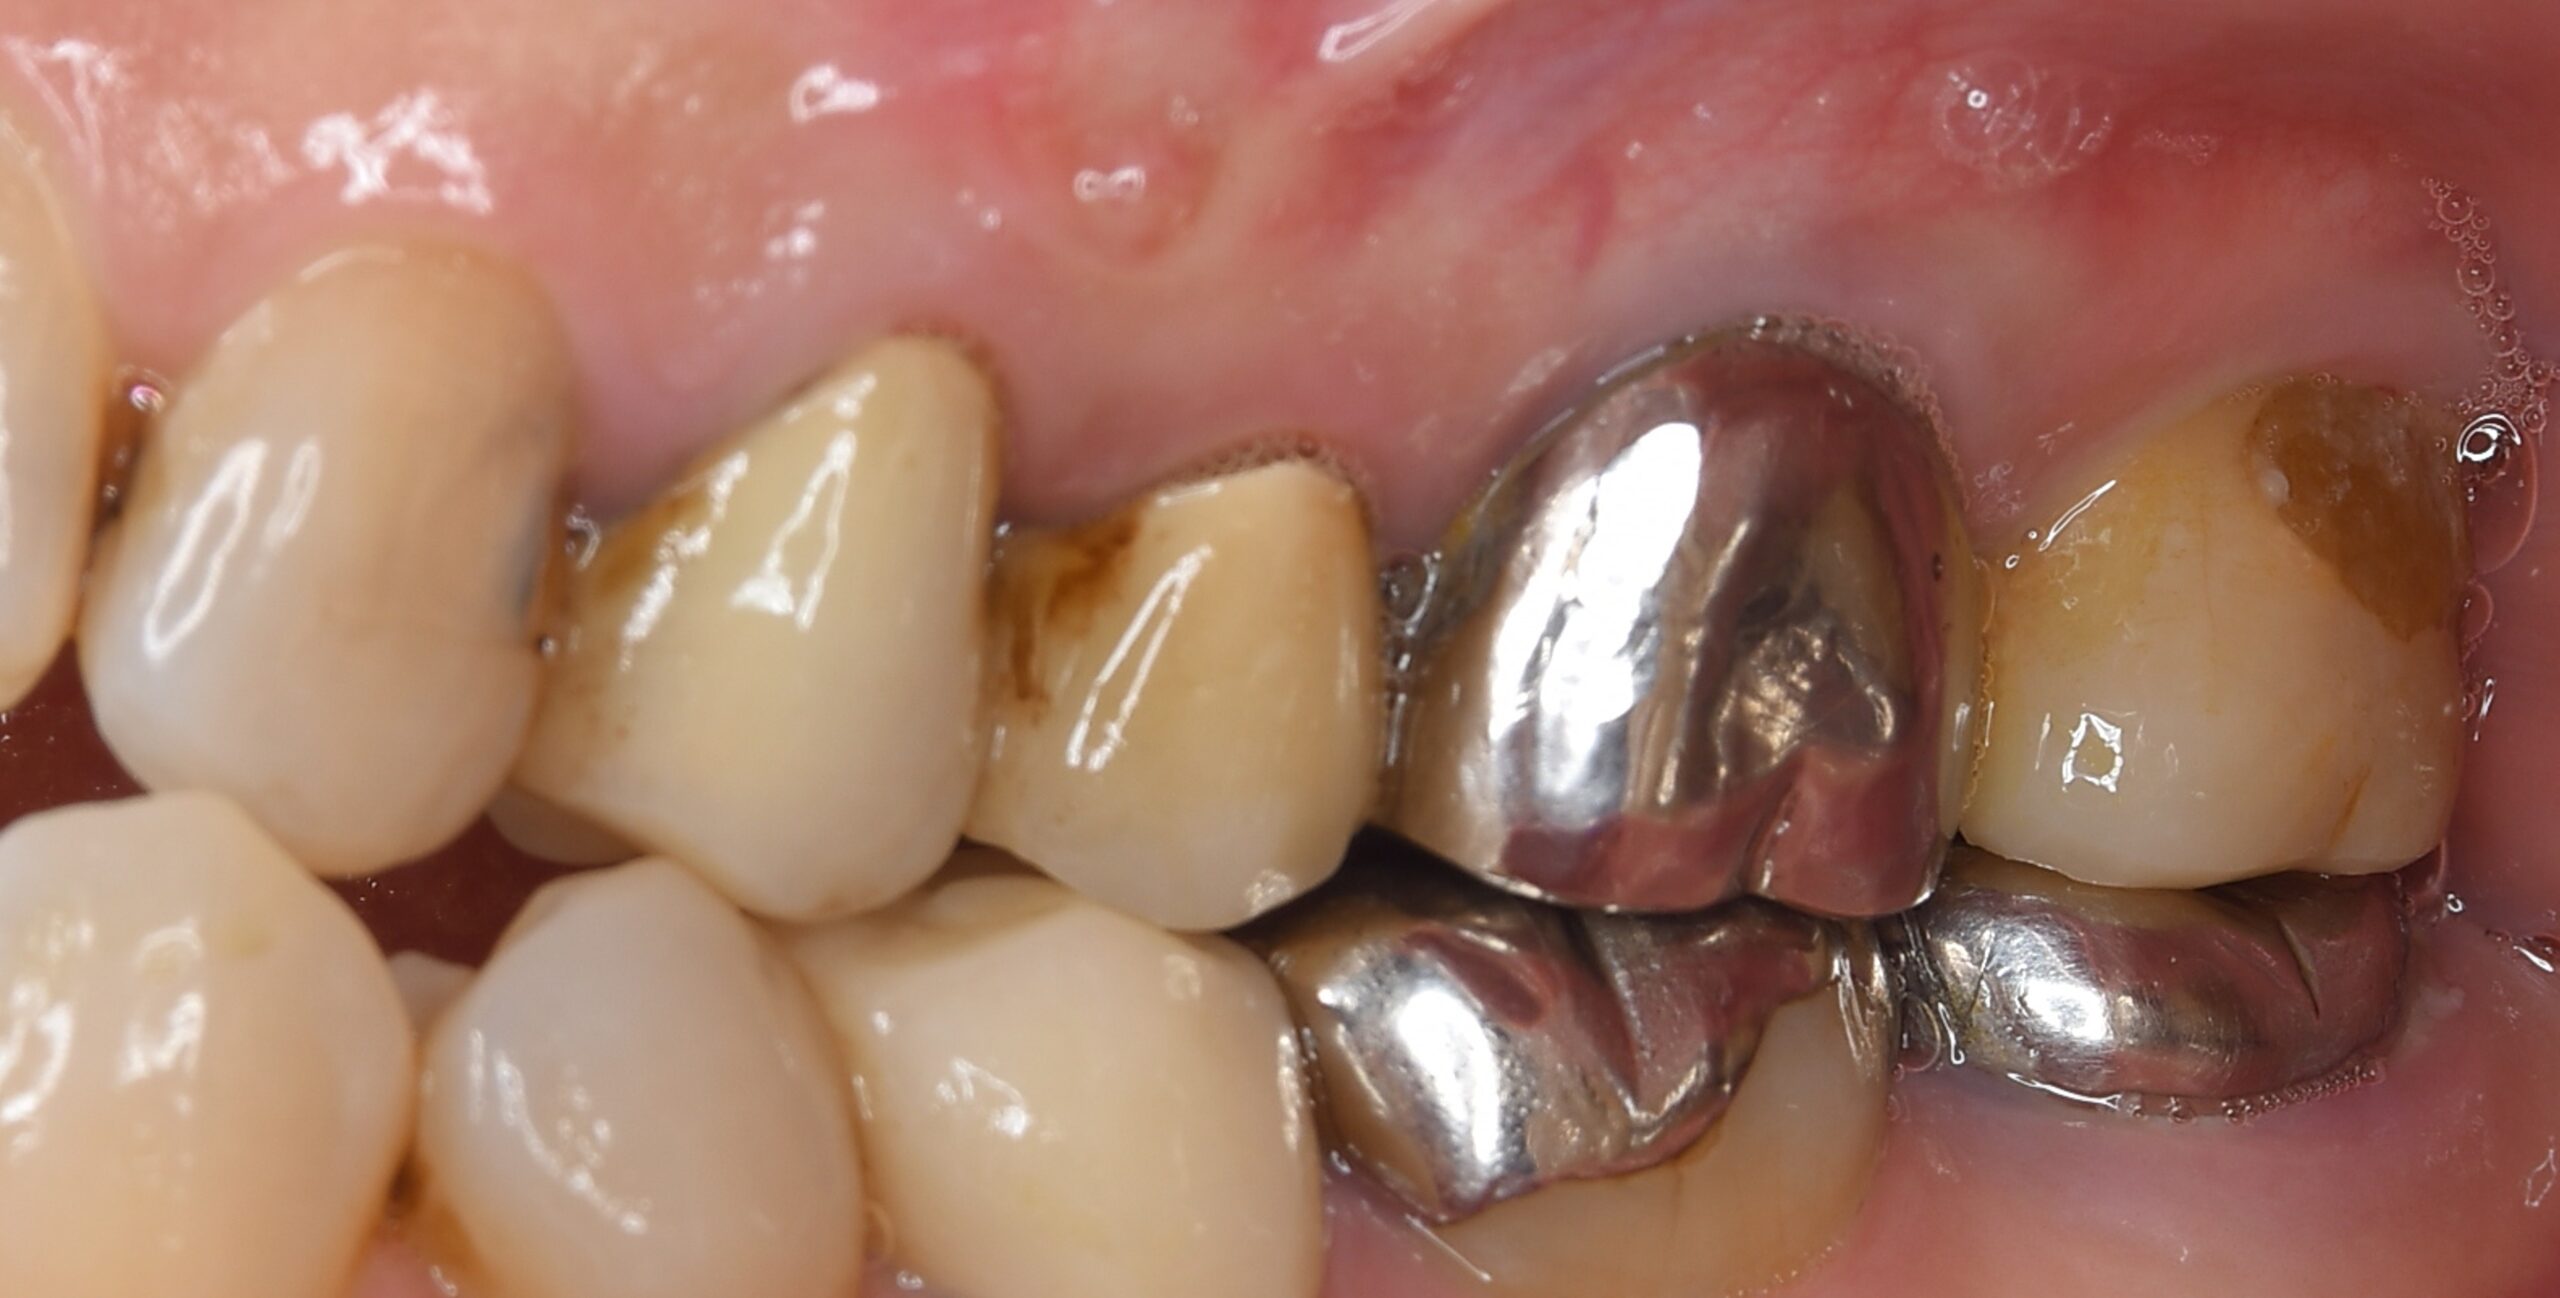

| 患者様データ | 60代 女性 |

| 来院時の主訴 | 「左上の歯が噛むと違和感がある。」 |

| 医院の診断 | 虫歯の再発、重度の歯周病を併発した慢性根尖性歯周炎 |

一般的に歯周病と根尖病変の混合病変は非常にシビアな状態と言われています。 この患者様の場合、根管治療だけでは歯の保存は不可能だったため、一度歯を抜歯し綺麗にしてから戻す歯牙再植という手法を用いて歯の保存を試みました。患者様の日々の歯磨きの努力もあり、健全な状態に改善することができました。 |